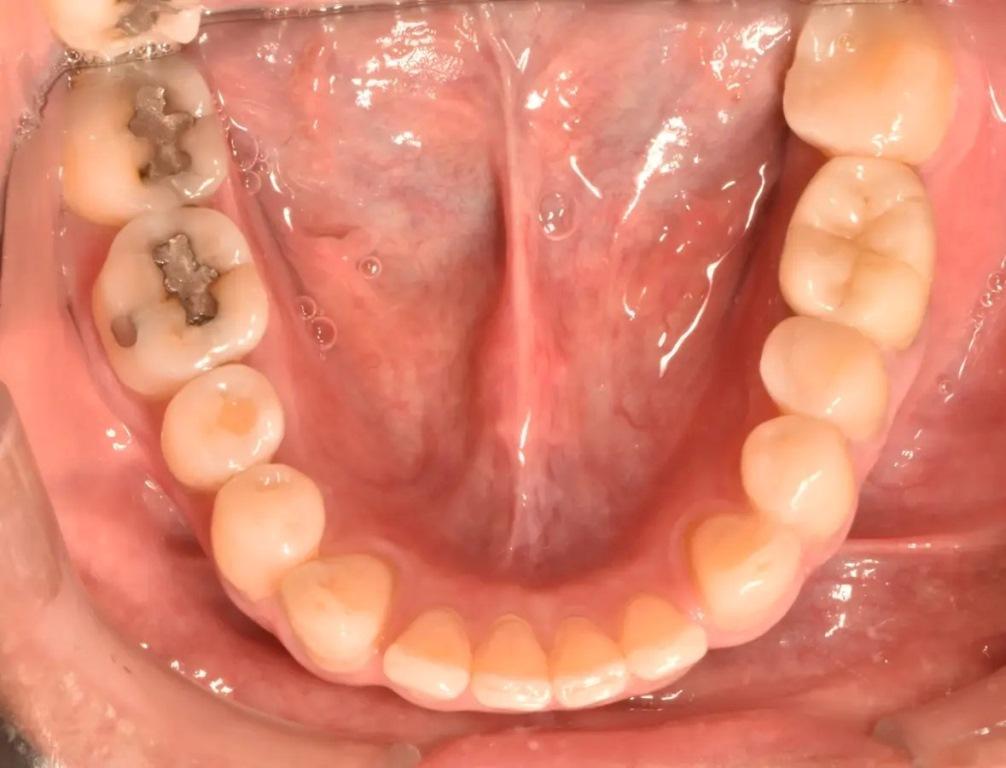

50-летний пациент с системным заболеванием, не вызывающим сопутствующих заболеваний, обратился с основной жалобой на боль при жевании. Он сообщил, что шесть месяцев назад ему была проведена прямая реставрация первого коренного зуба левой нижней челюсти. При клиническом и рентгенологическом обследовании была обнаружена большая, чрезмерно растянутая пломба из амальгамы II класса, а также J-образное просвечивание дистальной части зуба (фото 1). Также наблюдались дистально ориентированная буккальная припухлость и признаки окклюзионного износа, характерные для бруксизма зубных рядов. Зуб болезненно реагировал на перкуссию и отрицательно реагировал на электрические и тепловые стимулы. При зондировании в области абсцесса был выявлен изолированный карман диаметром 9 мм (фото 2). У зуба был диагностирован некроз пульпы и периапикальный абсцесс, а также подозрение на VRF. Для подтверждения предполагаемого диагноза была подготовлена полость доступа под изоляцией коффердамом и под стоматологическим операционным микроскопом. Когда предыдущая реставрация была удалена, на дистальной стороне дна пульпы при увеличении в 10 раз была обнаружена линия продольной трещины.